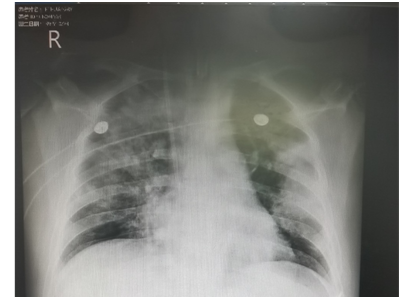

28岁的雷某近1个多月总是感觉口渴,于是猛喝奶茶、凉茶、可乐等饮料,可乐一天能喝1.5升,然而口渴症状未见减轻体重却下降大约8斤。突然有天昏迷不醒被家属送往医院,才发现是2型糖尿病酮症酸中毒,合并急性肾衰竭、急性心力衰竭、肺部感染、急性呼吸衰竭等多个脏器功能衰竭。